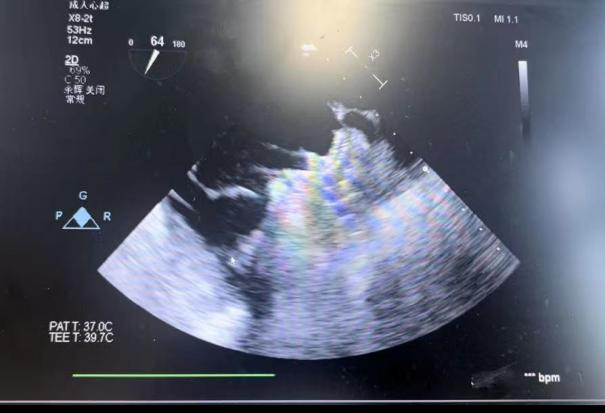

在食道超声引导下进行房间隔穿刺,由于心耳为反鸡翅型,穿刺位点需靠下靠前,潘教授先在90度双腔切面将定位靠下,再在45度主动脉短轴切面将定位靠前。穿刺成功后上导丝交换先健LAnavi™分段控弯导引系统送至心耳口部,经过A、B双弯的调整使得鞘管轴向与心耳同轴,获得理想封堵位置。然后推送钢缆释放出固定盘,锚定后退鞘释放出封堵盘。超声下观察贴合良好,无明显残余分流,牵拉测试稳定,即释放左心耳封堵器。释放后再次通过超声各个角度进行验证,封堵结果完美有效,整个过程一气呵成,手术取得了极大的成功。

牵拉测试稳定 完美有效封堵